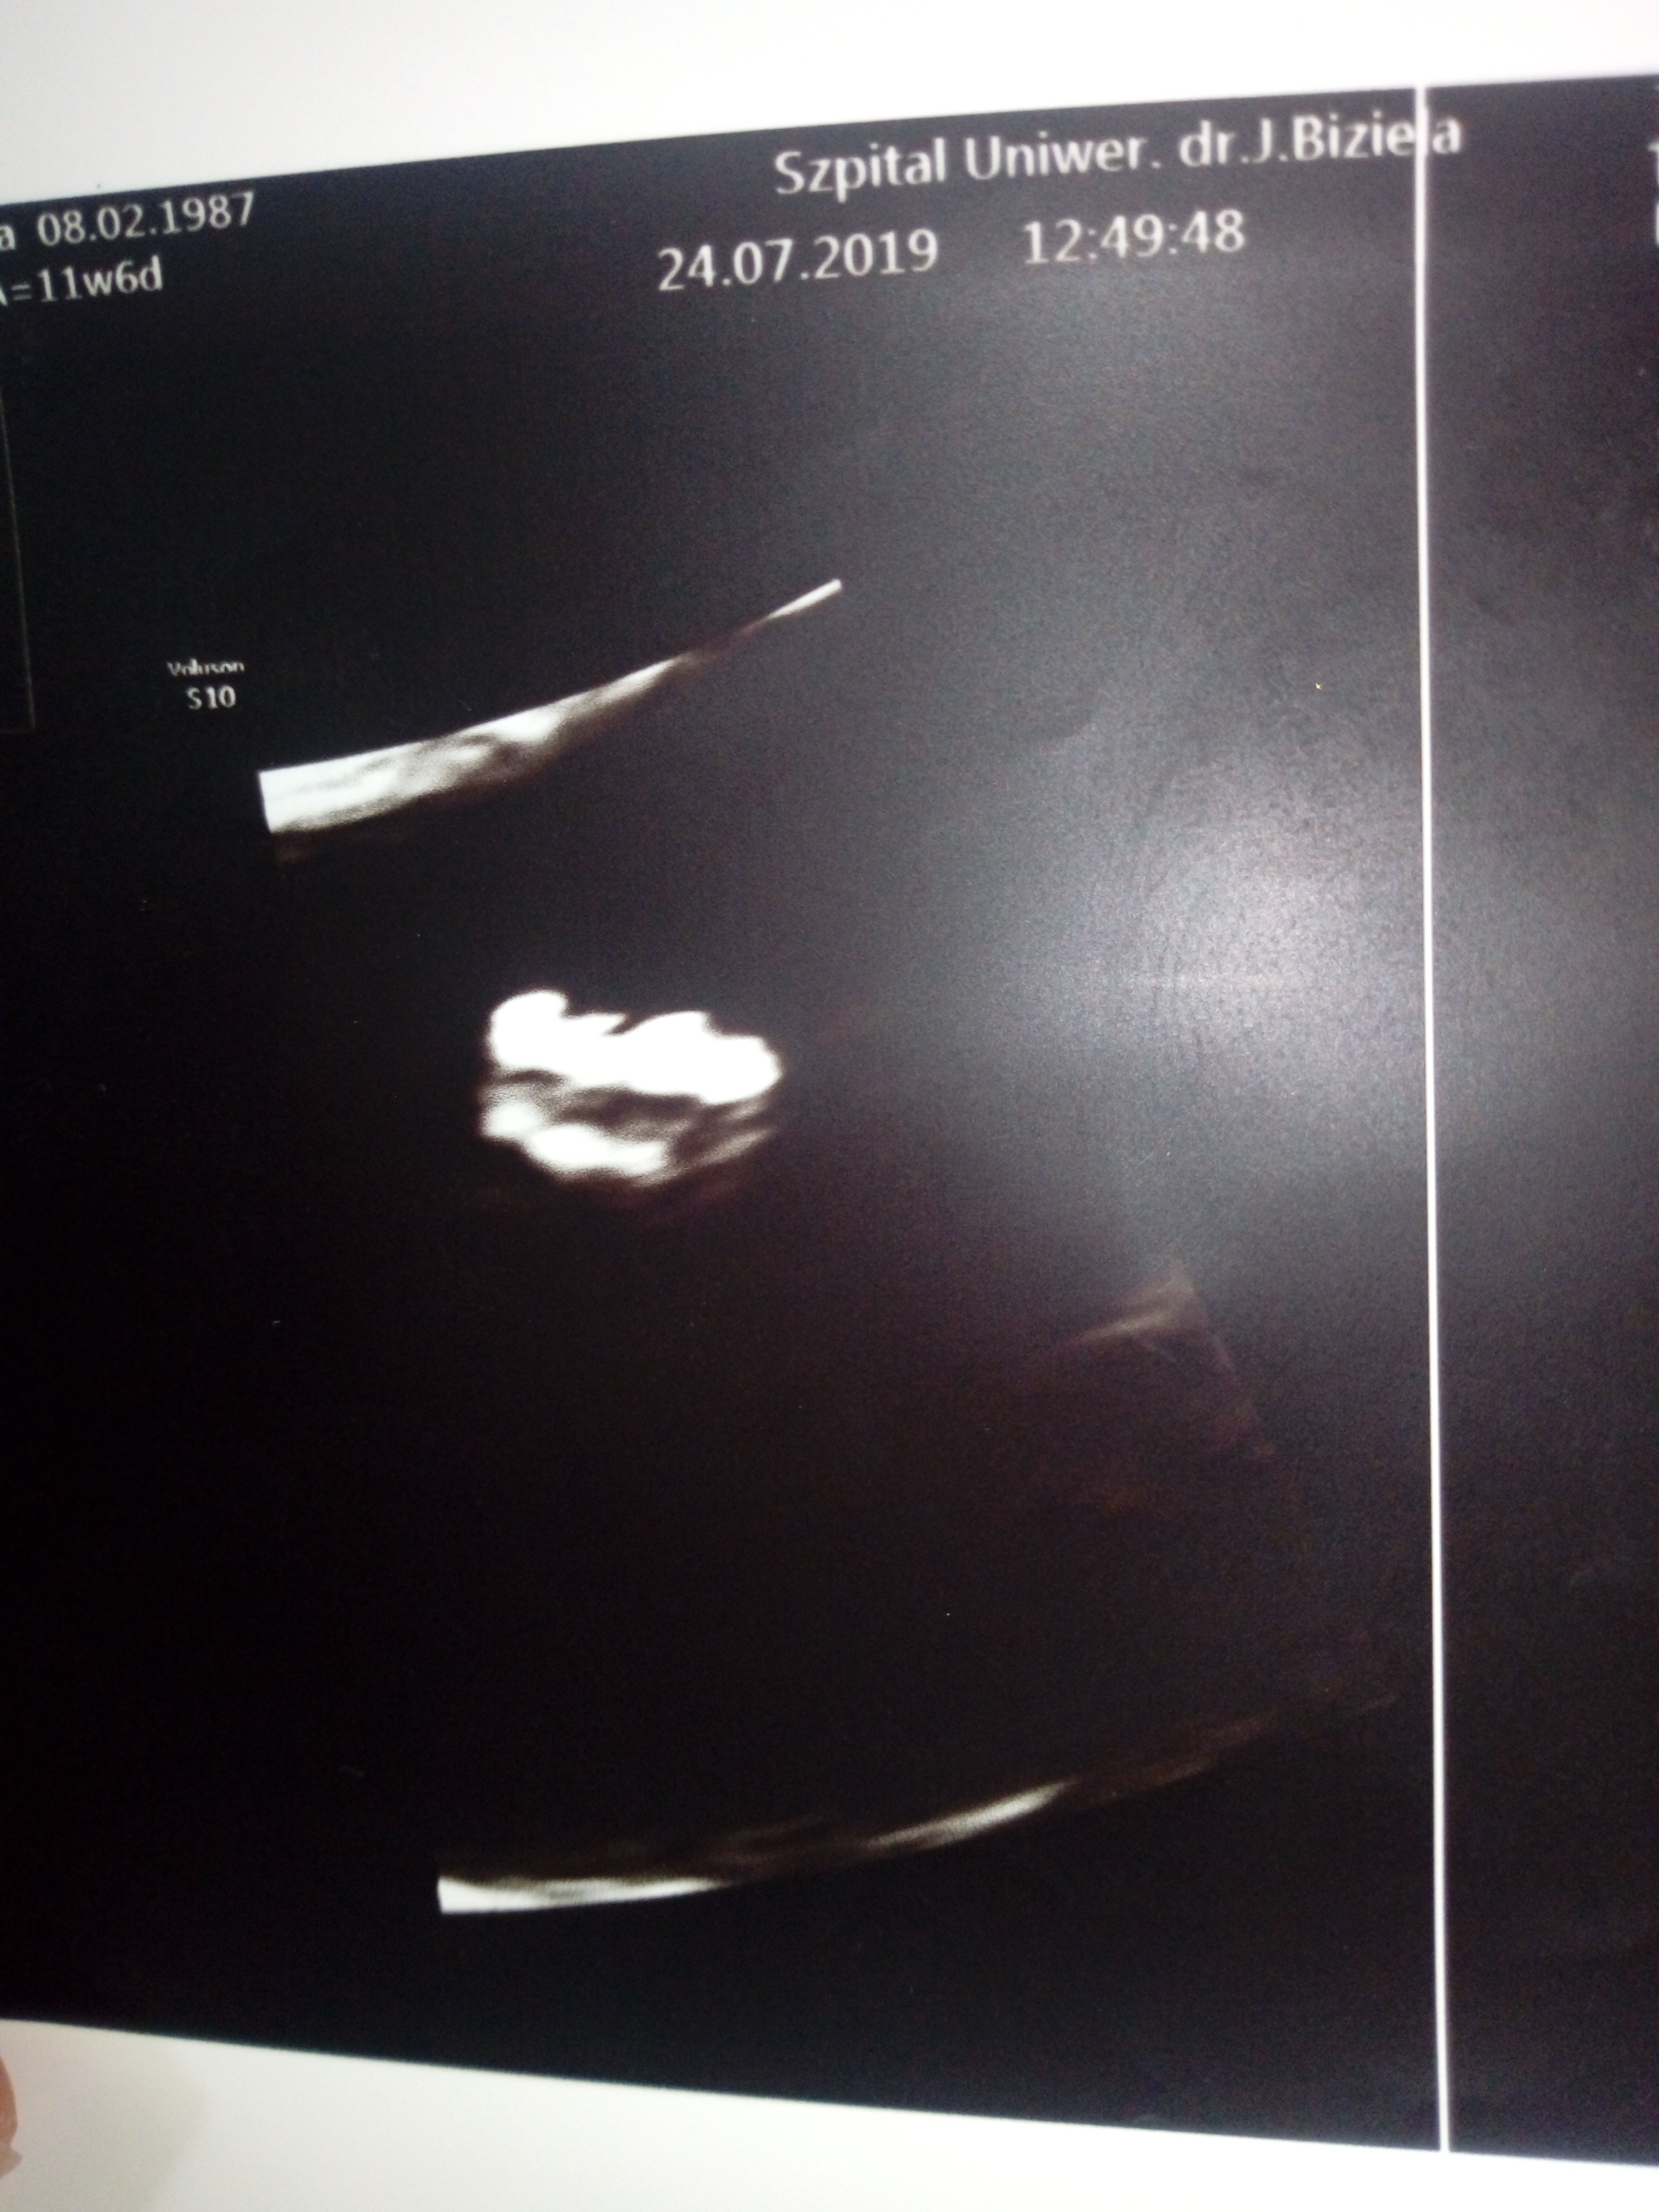

Cześć, znalazlam to forum po przekopaniu chyba całego netu w poszukiwaniu pomocy,rady,wsparcia?mam 32 lata,to moja 3 ciąża, z czego tylko jeden 7 mio latek w pelni zdrowy w domu, druga utracona w 7tc...Moj gin na rutynowej wizycie w 10 tc przyuwazyl NT rzędu 5,15 Kazal przyjechać po tygodniu gdzie NT wynioslo juz 2,4 Jednak mimo tego i jego zdaniem dobrego usg gdzie widzial kość nosowa,serce,narzady,rece,nogi wyslal mnie na prenatalne do Bydgoszczy do Biziela. Tam pani dr robila usg przez brzuch, przez pochwe i znowu przez brzuch bo male sie wiercilo Pomiary Nt wychodziły od 2,5 do 2,8 i tak w końcu wpisala Do tego obrzęk w okolicy karku plodu, Dv serca 1,29 Z uwagi na to WsZystko zalecila amnio ktore mam miec w dniu odbioru testu pappa po konsultacji z genetykiem....Boje sie tego badania poniewaz mam jelito drażliwe,od początku ciąży mam bóle brzuchu,zaparcia,skręty jelit...Mój gin mowi ze mogę zrobić test z krwi Nifty lub sanco Ale jeśli wyjdzie i tak wada to amnio mnie nie ominie jesli zdecyduje sie na terminacje ciąży...mam tydzień czasu na podjecie decyzji, przeczytałam większość wpisów tutaj Dziewczyny mowia ze badanie nic przyjemnego ale do przeżycia i u nich obylo sie bez powikłań...Doradzcie czy test z krwi Sanco czy amnio?

Usg prenatalne mialam juz we właściwym tyg czyli 11+6, Teoretycznie mam tylko opis badania usg ,ponieważ kolejka szla w,szpitalu w ten sposób ze najpierw mialam genetyka a potem po ok godzinie dopiero usg prenatalne wiec ryzyka oszacowanego typowo nie mam Zalaczam zdjecia dzidzi i opisu .Co do decyzji to została ona podjeta juz nawet przed ciążą,co by było gdyby....I moze zostanę zlinczowana przez kogos ale nie chodzi tu o mnie,o mój egoizm Myślę raczej całościowo Nie chce straszaka w przyszłości ewentualnie obarczac opieka nad chorym rodzeństwem...Poprostu nie...

W środę mam najpierw wyniki pappa, rozmowę z genetykiem i później ewentualnie amnio...Ja wiem ze nikt nie moze podejmowac decyzji za mnie Jestem tego świadoma